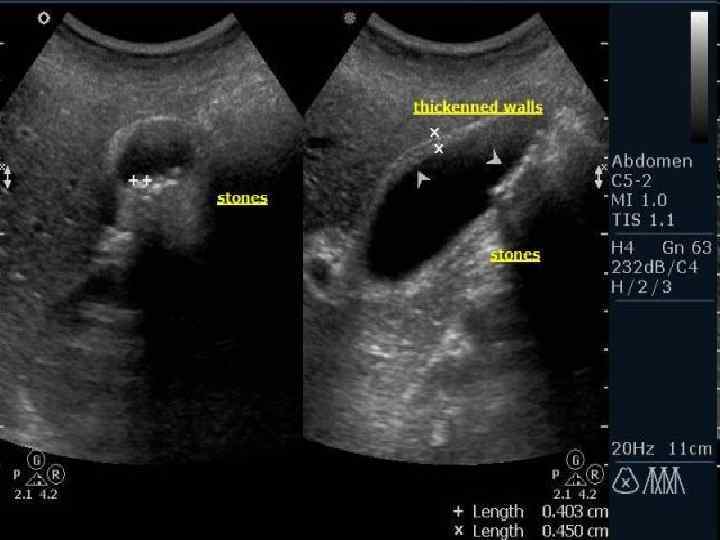

Острый холецистит • Локализация боли в правом верхнем отделе живота • Иррадиация в правое плечо и лопатку • Тошнота и многократная рвота с симптомами раздражения брюшины или без таковых. • Положительны симптомы Грекова-Ортнера, Образцова, Кера и др. • Лейкоцитоз со сдвигом формулы влево и увеличение СОЭ. • Наиболее надежным и доступным диагностическим приемом в данной ситуации является ультразвуковое исследование.

УЗИ желчного пузыря при остром холецистите. Выявляется растянутый желчный пузырь (толстая стрелка) с камнем, вколоченным в устье пузырного протока (тонкая стрелка), отбрасывающим акустическую тень. Стенка желчного пузыря значительно утолщена.

Ультразвуковыми признаками острого холецистита являются • • • утолщение стенок желчного пузыря более 4 мм "двойной контур" стенки увеличение размеров желчного пузыря перивезикальной жидкости положительный УЗ-признак Мерфи (локальное напряжение желчного пузыря под УЗ-датчиком). • По данным УЗИ можно судить о форме воспаления желчного пузыря